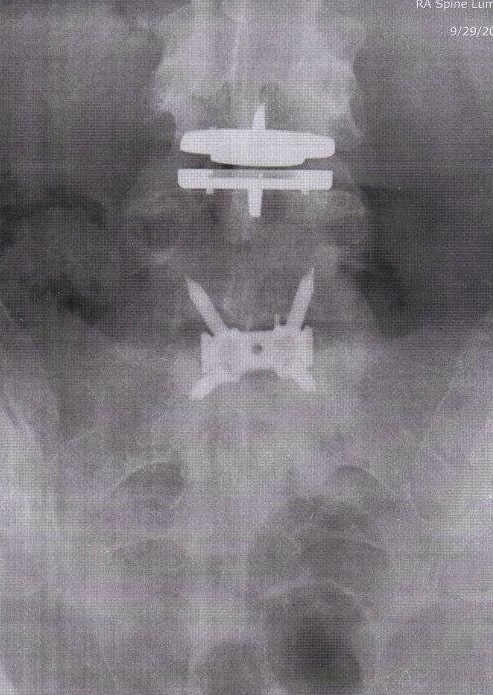

This x-ray was taken 6 weeks post-op. Spinal fusion with instrumentation L4/5-L5/S1, disc replacement L3/4